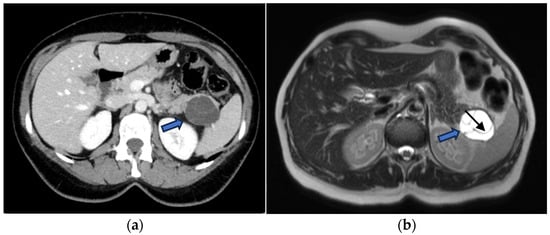

MCNs typically present as multiloculated macrocystic lesions due to the presence of thick internal septa. Peripheral calcifications (found in approximately 25% of cases) are considered pathognomonic and enable a definitive diagnosis (Figure 7).

Figure 7.

(a) Axial CECT scan of a 50-year-old-woman shows a large (40 mm), multiloculated lesion located in the pancreatic tail (blue arrow); (b) MRI demonstrates a well-circumscribed, multilocular cystic lesion with thick internal septa (black arrow), showing hyperintense signal on T2-w images.

Figure 8.

CECT of a 49-year-old woman shows a cyst-like lesion with a calcified wall (arrow) in the pancreatic tail (a). In the arterial (b) and venous (c) contrastographic phases, mall enhancing mural nodules are observed.